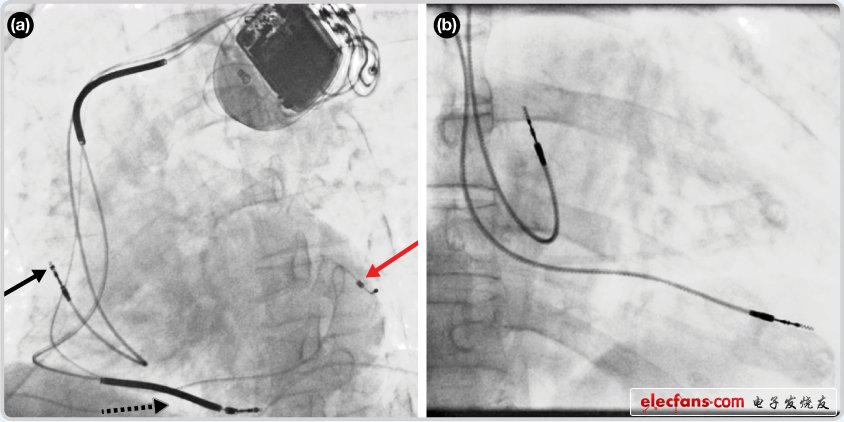

1354 研究人員表示,這是首次實現(xiàn)利用消融導(dǎo)管結(jié)合近紅外光譜學(xué)映射,成功區(qū)分心捐贈與心血管疾病患者各種組織的類型。目前,大多數(shù)臨床心臟測繪系統(tǒng)都是基于功能測量,如能將提供底層組織組成信息的光學(xué)測量與標(biāo)準(zhǔn)功能方法共同使用,可以顯著提高消融成功率。

2020-07-31 17:01:21

臨床試驗,如果一切進(jìn)展順利的話,利用它能擴(kuò)展主治醫(yī)生的視野,更好的檢測病人的心臟情況,病人也不再需要重復(fù)進(jìn)行心臟電燒手術(shù),這樣既可以減少住院次數(shù),還能降低醫(yī)療成本,對醫(yī)生和病人來說,都是一個福音。由此可以看出,傳感器技術(shù)不但能改善生活質(zhì)量,還能降低人類面臨的痛楚。